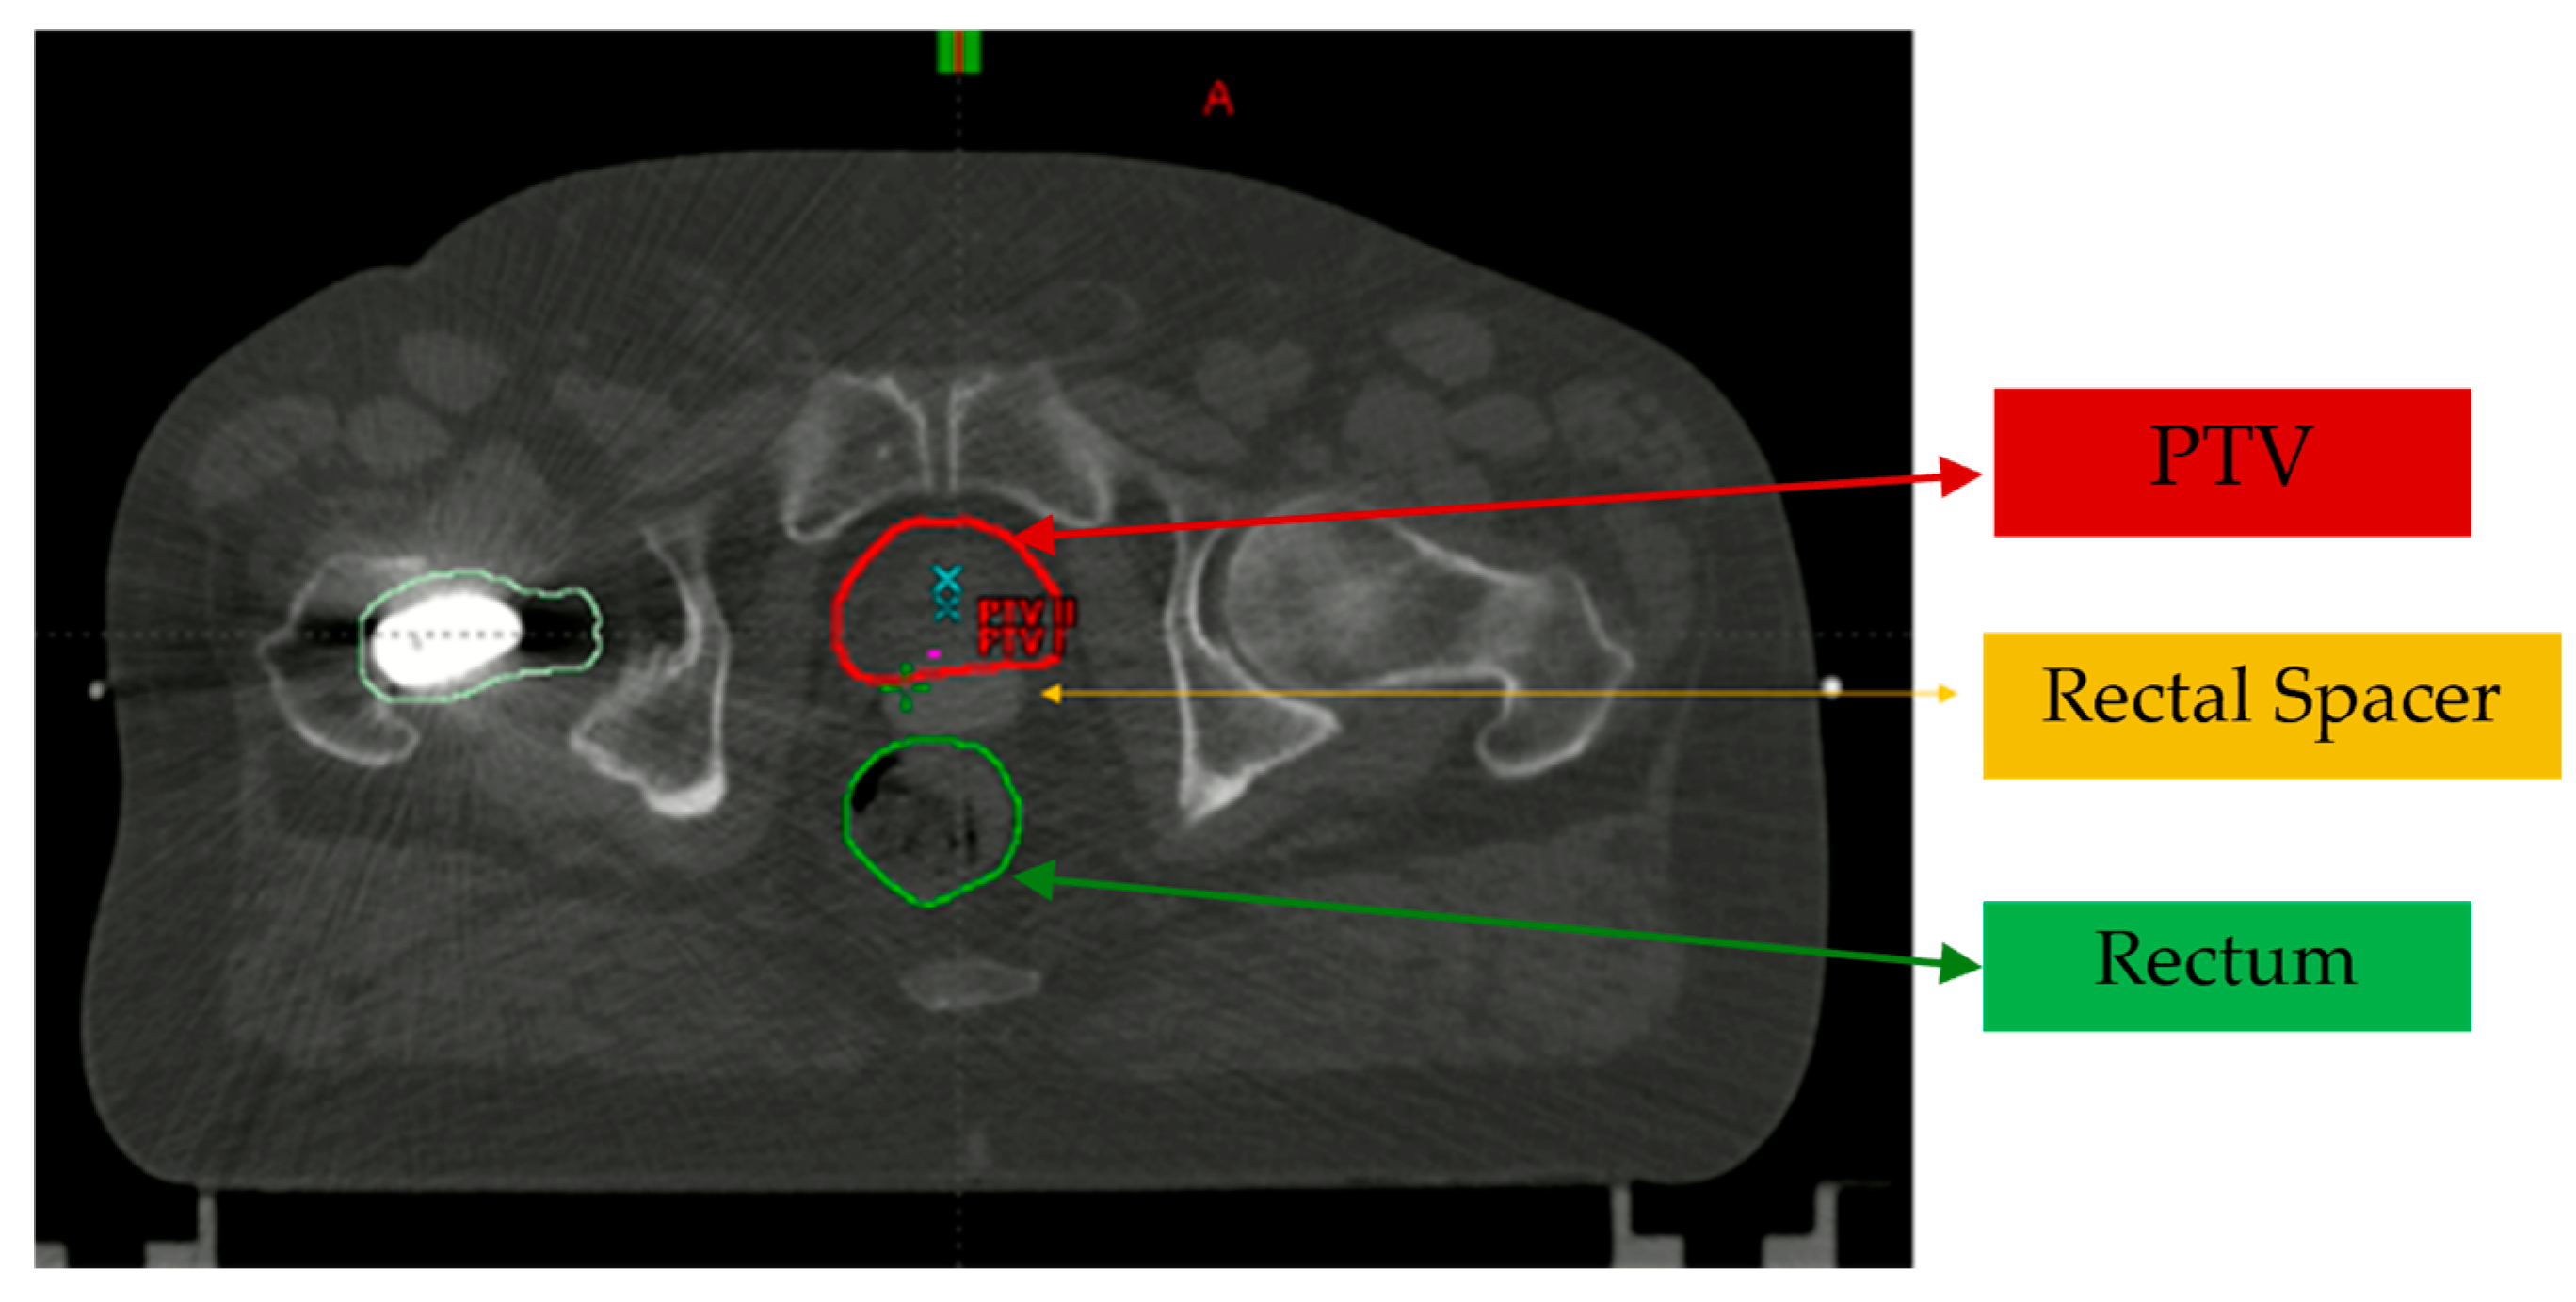

In patients undergoing VMAT with a rectal spacer, a minimally invasive procedure is performed to insert the spacer between the prostate (outlined in red) and the rectum (in green). This spacer serves to reduce rectal radiation exposure during treatment (see Figure 1).

Figure 1. Axial pelvic slice showing the location of the rectal spacer in Eclipse Planning System version 15.6 by Varian Medical Systems.